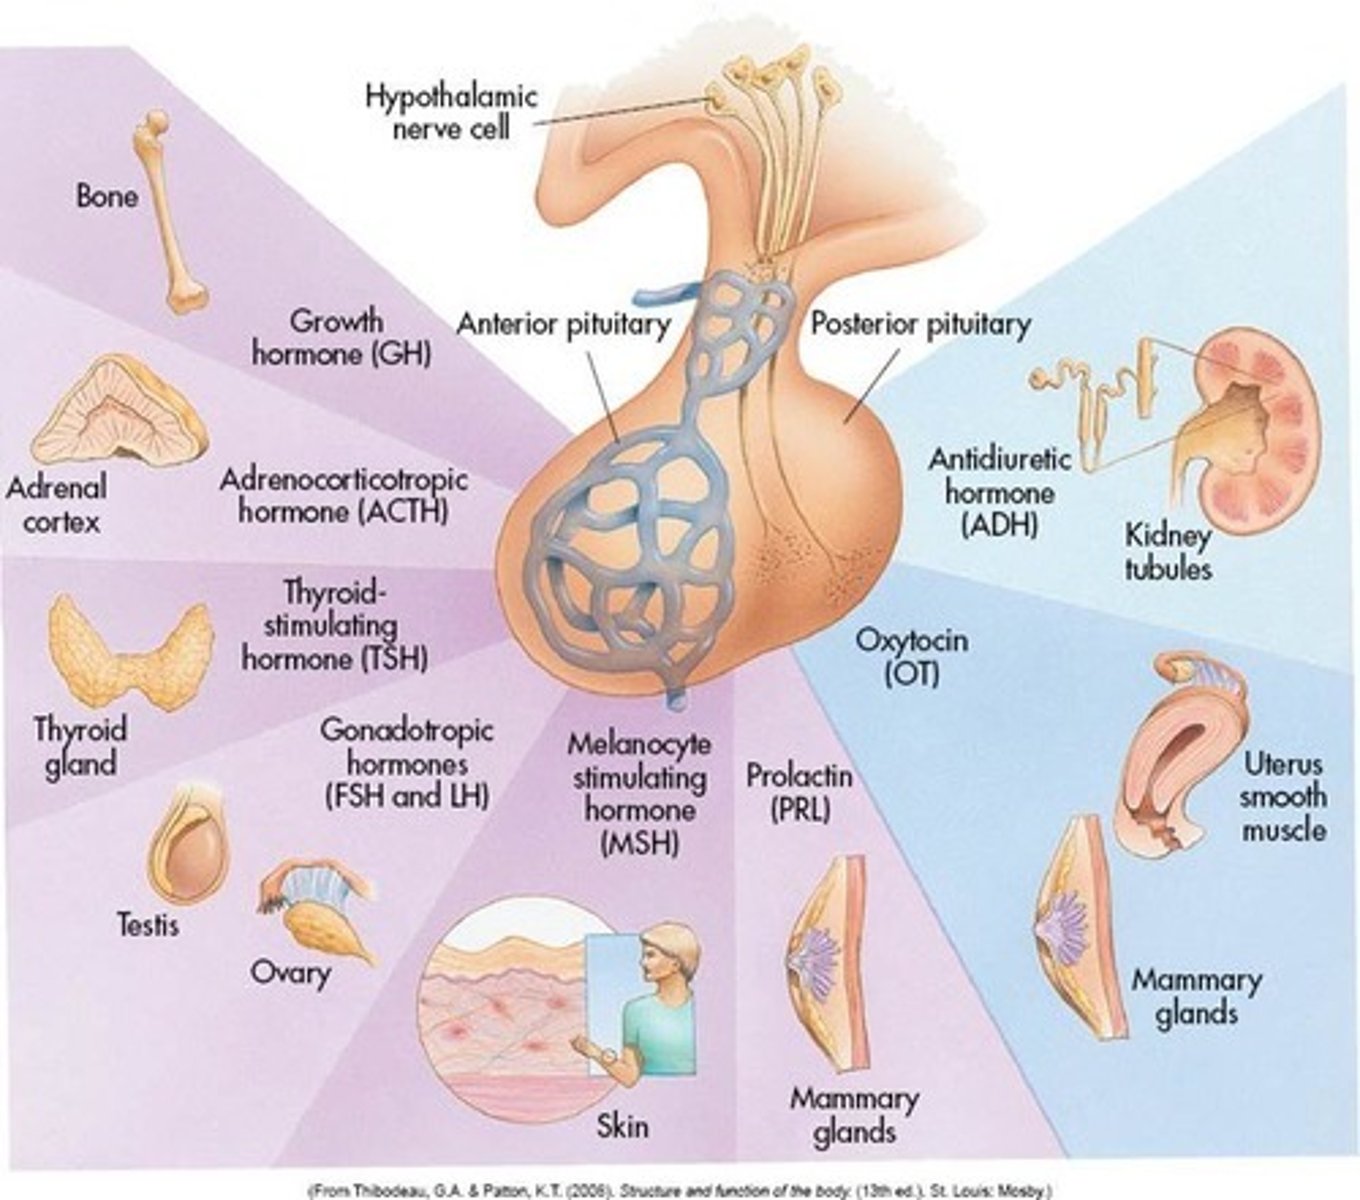

pituitary gland

gland at the base of the brain that dangles under the hypothalamus

pituitary gland hormones

LH, FSH, GH, TSH, ACTH, Prolactin, Oxytocin, ADH

hypothalamus hormones

ADH, oxytocin, regulatory hormones

Testes

male gonads

Ovaries

female gonads

thyroid gland

endocrine gland that surrounds the trachea in the neck

Adrenal Glands

a pair of endocrine glands that sit just above the kidneys

testes produce

testosterone

ovaries produce

estrogen and progesterone

thyroid hormones

T3, T4, calcitonin

adrenal glands hormones

Epinephrine, norepinephrine, glucocorticoids- cortisol, mineralocorticoids- Aldosterone